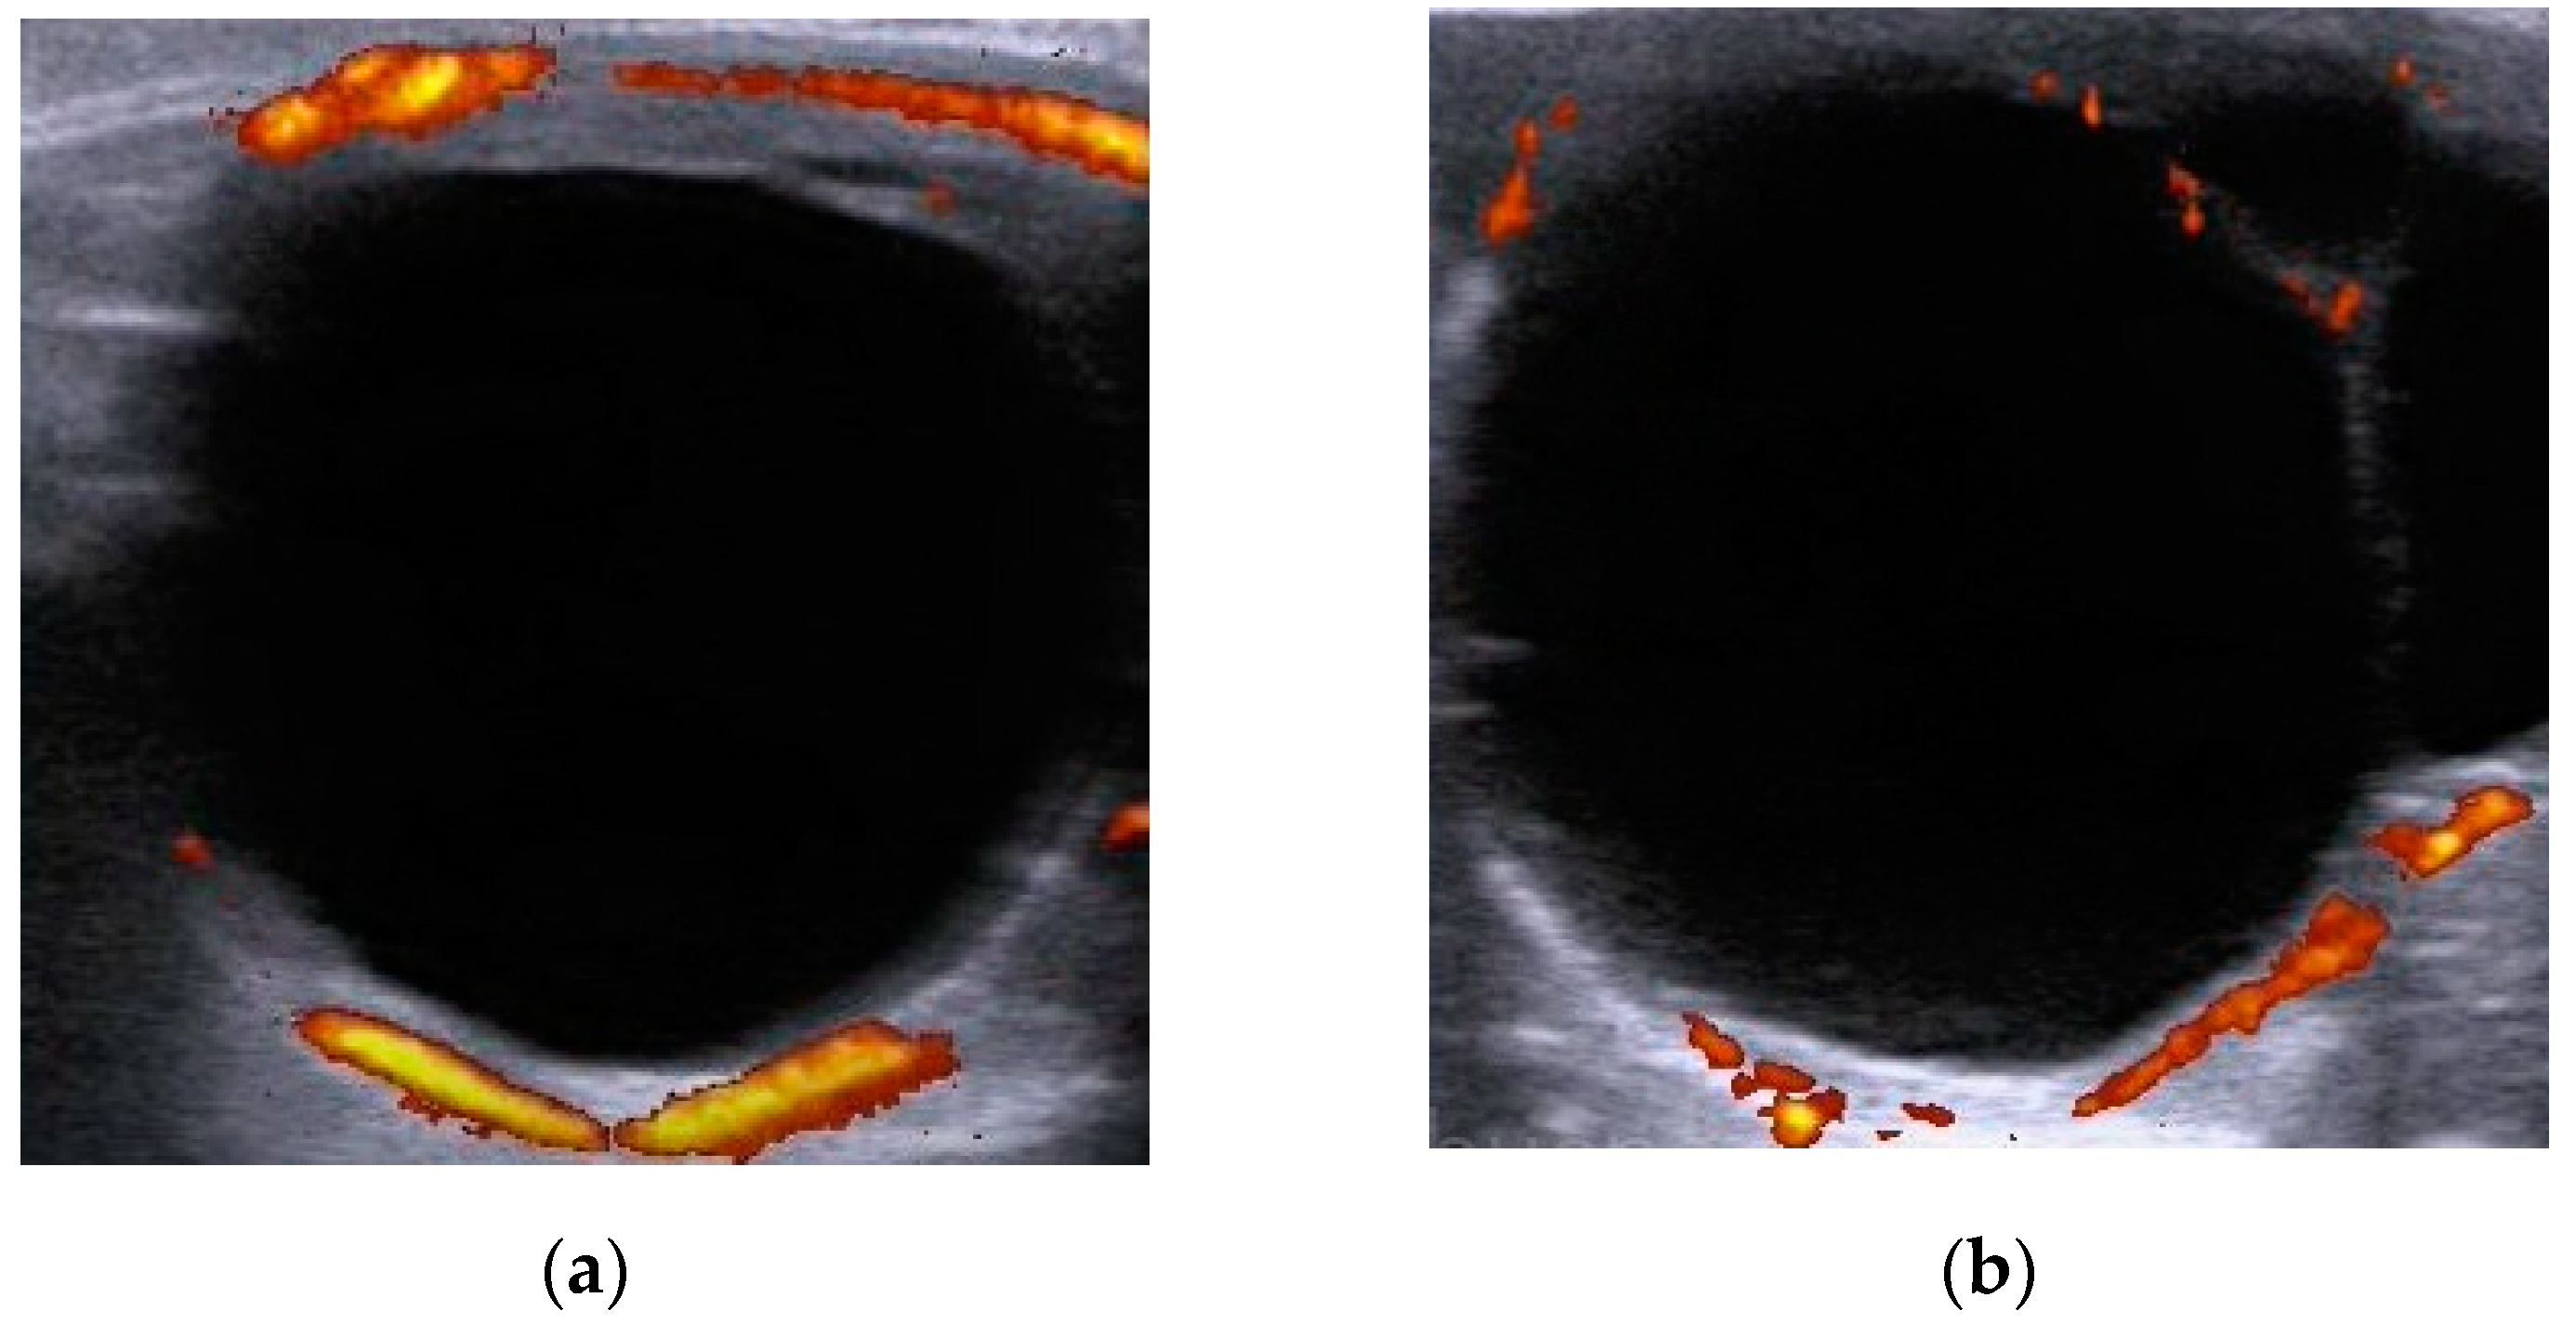

2.3. Ultrasonography